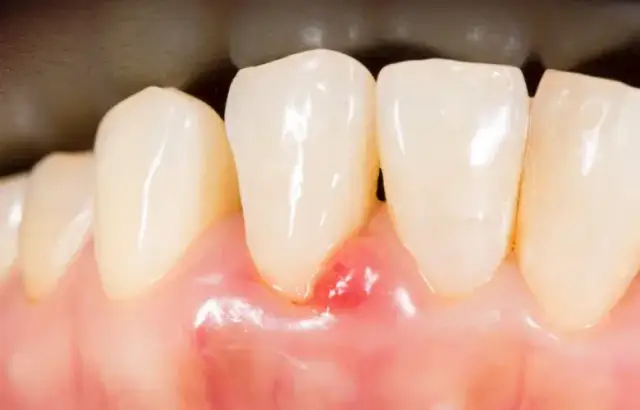

Aby rozpoznać raka dziąseł, należy zwrócić uwagę na konkretne cechy guzków i owrzodzeń. Guzki mogą mieć różne rozmiary – od kilku milimetrów do kilku centymetrów. Ich kolor może się różnić, od białego przez różowy, aż po ciemnoczerwony. Tekstura guzków może być twarda lub miękka, co również jest ważnym czynnikiem w rozpoznawaniu. Owrzodzenia z kolei często mają nierówne brzegi i mogą wydzielać nieprzyjemny zapach, co jest oznaką stanu zapalnego.

- Guzki na dziąsłach mogą być twarde i zgrubiałe, co jest typowe dla raka.

- Owrzodzenia, które nie goją się przez dłuższy czas, powinny wzbudzić niepokój.

- Obecność białych lub czerwonych plamek na dziąsłach to dodatkowy sygnał, który należy zbadać.

W celu lepszego zrozumienia, jak wygląda rak dziąseł, warto zapoznać się z przykładami zdjęć zmian nowotworowych. Takie obrazy mogą ukazywać różnorodne formy zmian, od guzków po owrzodzenia, które są kluczowe dla wczesnej diagnozy. Na przykład, zdjęcia mogą przedstawiać twarde guzki w okolicy zębów trzonowych oraz owrzodzenia, które nie goją się przez dłuższy czas. Obserwacja tych zmian jest istotna, ponieważ mogą one wskazywać na zaawansowany stan choroby.

Jak interpretować zdjęcia raka dziąseł – kluczowe cechy

Interpretacja zdjęć zmian nowotworowych na dziąsłach wymaga uwagi na kluczowe cechy, które mogą wskazywać na obecność raka. Przede wszystkim, należy zwrócić uwagę na kształt zmian; guzki powinny być twarde i zgrubiałe, a owrzodzenia mogą mieć nierówne brzegi. Kolor zmian również ma znaczenie – zmiany mogą być białe, czerwone lub ciemnoczerwone, co może sugerować różne stany patologiczne. Ponadto, ważne jest, aby ocenić, czy zmiany są statyczne czy też się rozwijają, co również wpływa na diagnozę.